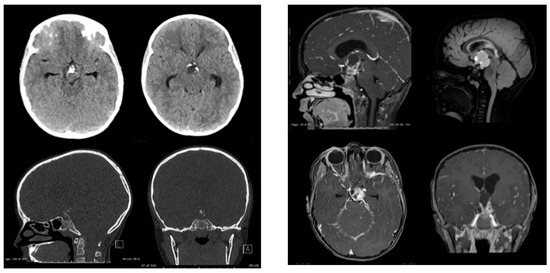

The Inflammatory Milieu of Adamantinomatous Craniopharyngioma and Its Implications for Treatment